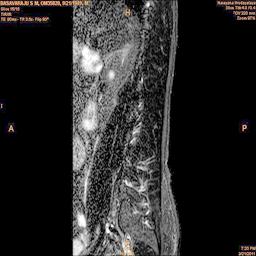

The developed algorithm presented in the previous section was coded using Matlab Version 8.0. The experiment was conducted by considering poor quality spinal cord images of having various lesions. The first column of Fig. 4 shows the axial view of neck spinal cord images of size pixels, respectively. The second column of Fig. 4 presents the same images enhanced using histogram equalization. As is evident from the results presented, the histogram equalization method performs global image enhancement operation which improves the contrast of an image but at the cost loss in image details. The third column of Fig. 4 shows the MSR based spinal cord image enhancement. It can be seen that from the result presented, MSR scheme improves the details that are not clearly visible in histogram equalization technique. In general, image enhancement achieved by MSR method is better compared to histogram equalization. However, the MSR method voilates gray world assumption. Therefore, the image enhanced by this scheme appears to be grayish. Although, numerous work have been reported for solving the problem due to gray world voilation, no work seems to developed for complete elimination.

The fourth column of Fig. 4 shows the image enhanced using Chao et al. []. It can be seen from the results presented that the reconstructed images of Chao’s method have black spots. The appearance of these dark patches degrades the visual quality of the enhanced image. The image enhanced using proposed multirate multiscale retinex image enhancement method presented in the fifth column of Fig. 4, overcomes the drawback of the Chao’s method. As we can see from the simulation results, image enhancement achieved by the proposed method has improved details with significant contrast enhancement. The enhanced images from the proposed method provides information to physicians, radiologists and researchers for various types of pathology detection.